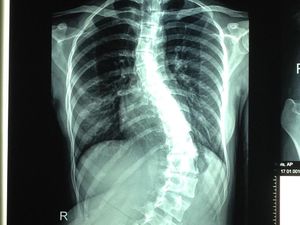

Jessica Mila Akui Idap Skoliosis, Begini Cara Deteksi Dininya

Aktris cantik Jessica Mila mengaku dirinya mengidap skoliosis, yakni kelainan tulang punggung dengan kondisi bengkok. Begini cara deteksi dini skoliosis.